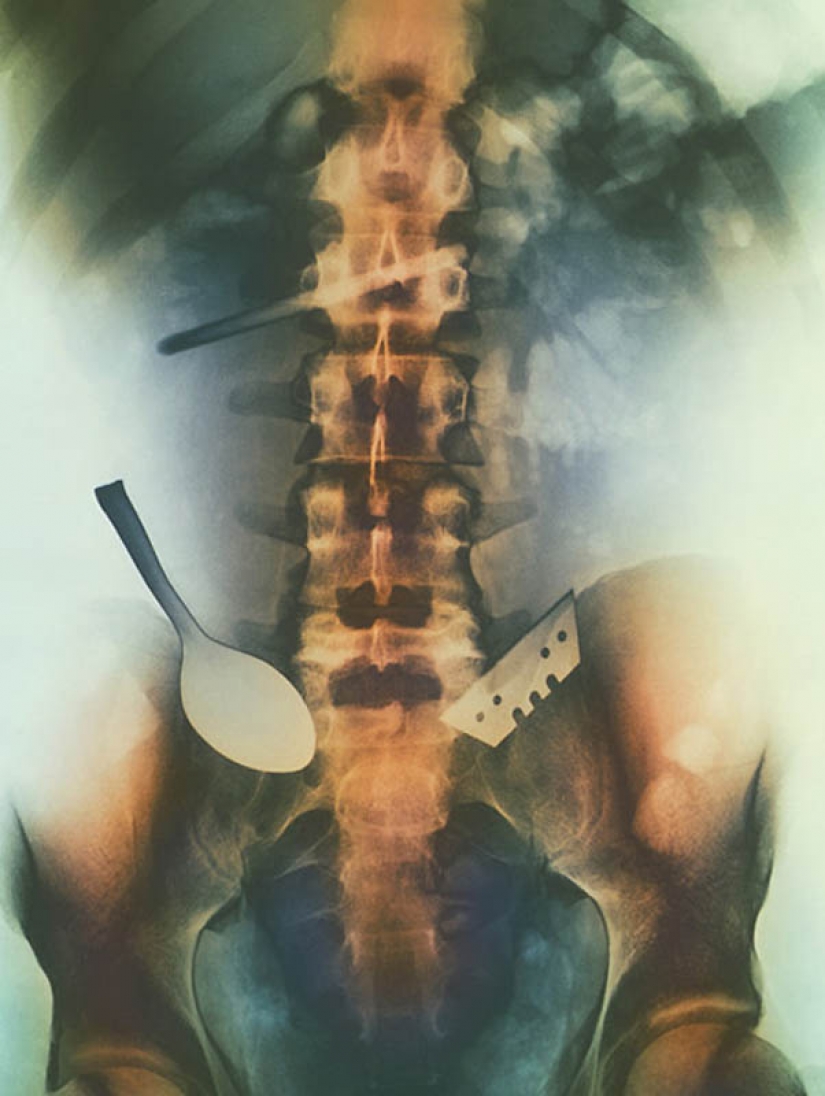

5. Color the objects that are swallowed by the patient, and stuck in his gut, including the spoon and the blade.